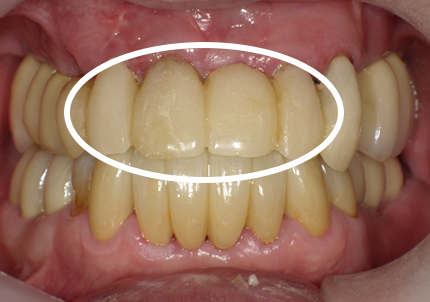

1.初診時口腔内写真(2018年10月)

➡審美領域における骨吸収を防ぐためのPET技法の歴史

近年、審美インプラント治療の進化により術者サイドの技術的、肉体的ストレスの軽減、患者サイドへの外科的侵襲度の劇的な軽減を可能とするテクニックが報告されている。審美領域で抜歯を行う際、束状骨の吸収により抜歯窩の形態を維持できず、唇・頬側の骨吸収が起こる。